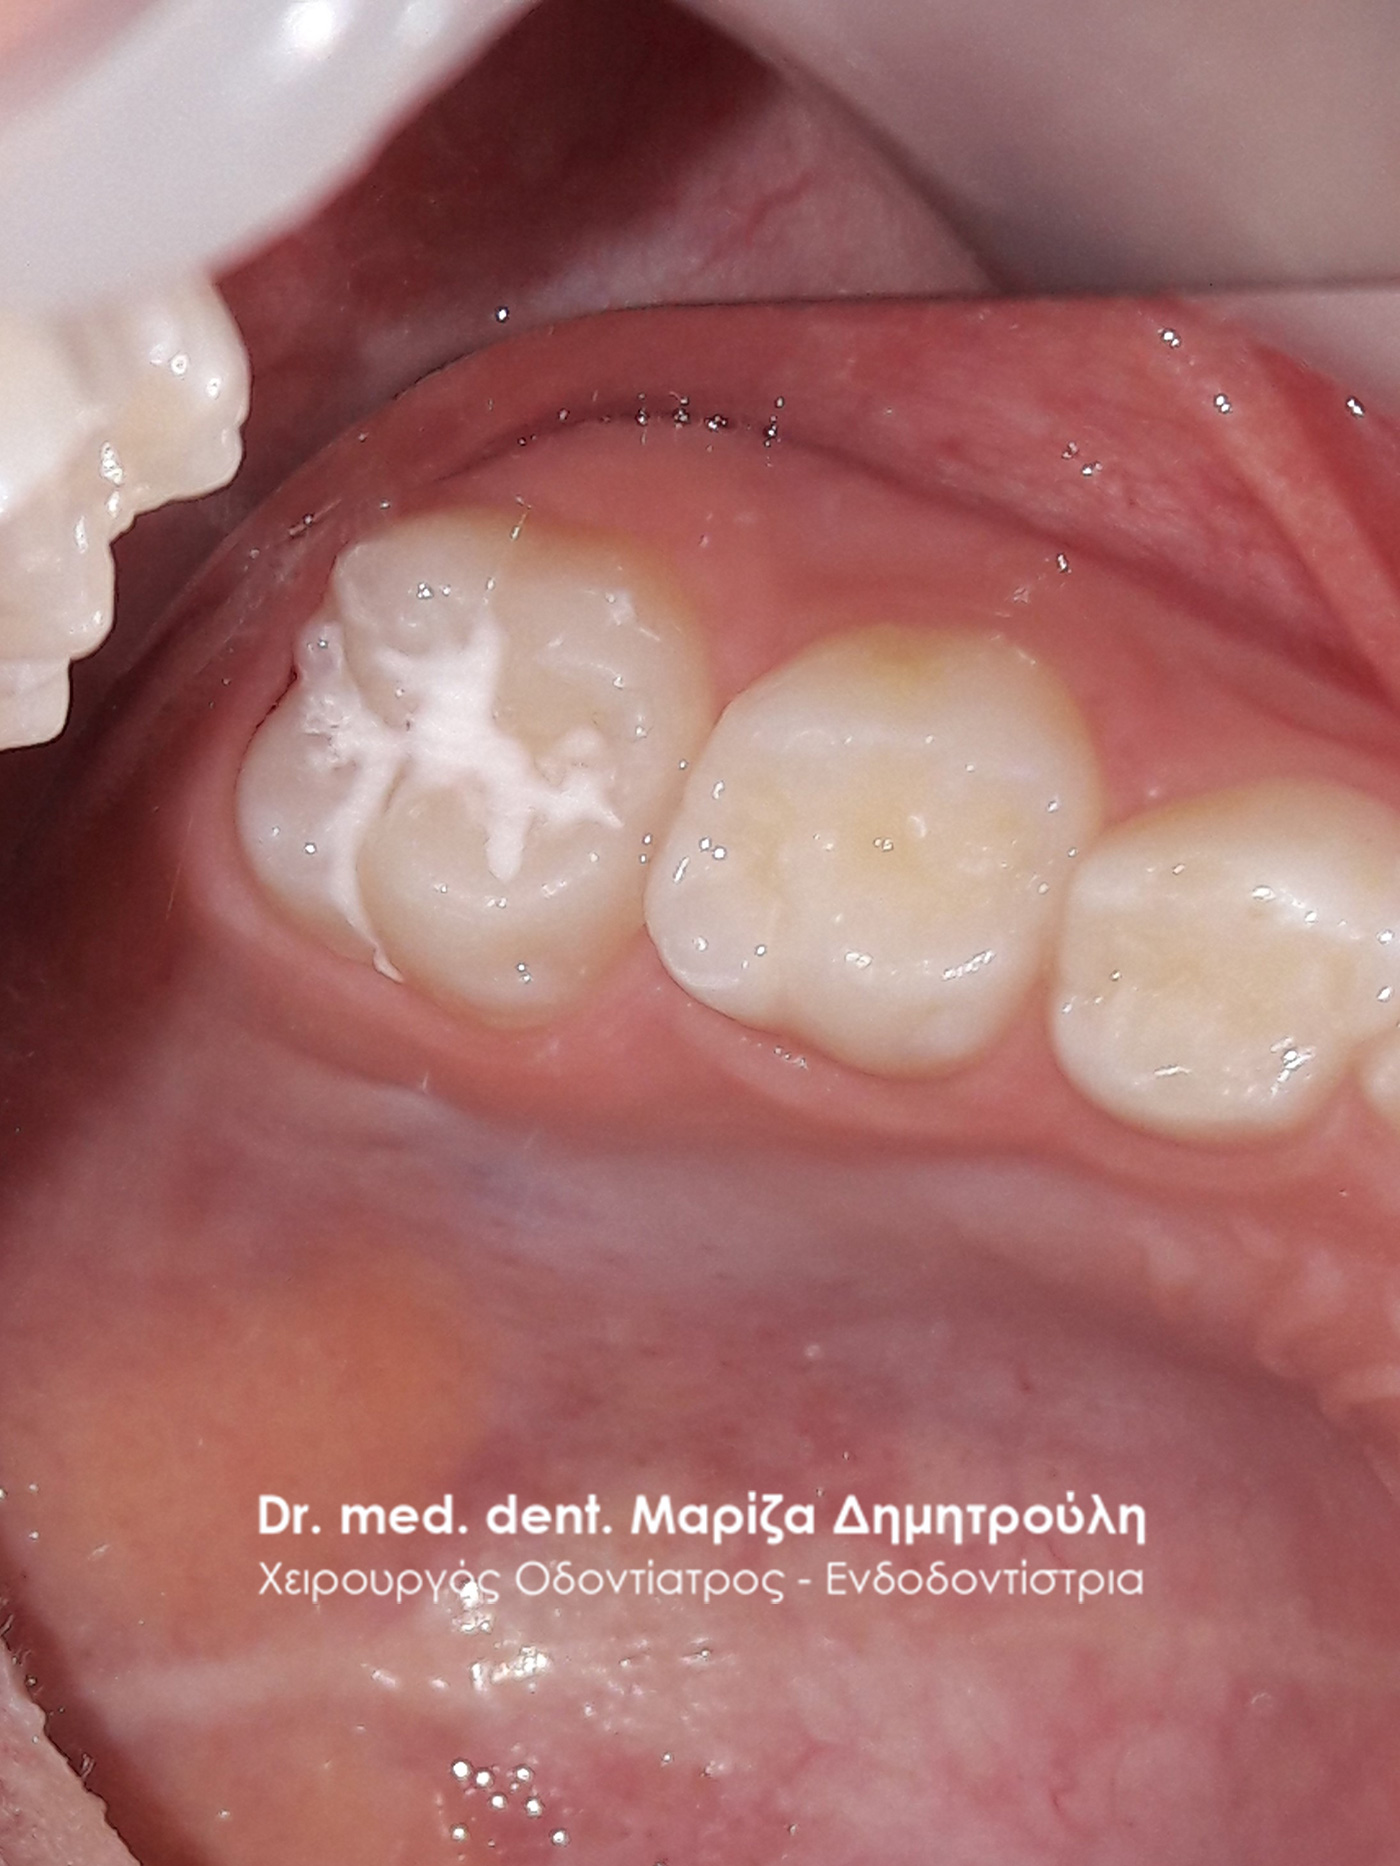

Περιστατικό – Sealant / προληπτική κάλυψη οπών και σχισμών

Στην έφηβη αυτή μικρή κυρία πραγματοποιήθηκε προληπτική κάλυψη της μασητικής επιφάνειας του μόνιμου άνω πρώτου γομφίου, για την προστασία του δοντιού από την τερηδόνα. Εφόσον η μασητική επιφάνεια ενός δοντιού καλύπτεται με υλικό sealant μειώνεται ο κίνδυνος προσβολής από τερηδονογόνα μικρόβια, καθώς συγκεντρώνονται λιγότερα μικρόβια και υπολείμματα τροφών στη μασητική επιφάνεια ενώ παράλληλα το παιδί μπορεί να βουρτσίζει πιο αποτελεσματικά και εύκολα. Ο χρόνος ζωής ενός sealant κυμαίνεται από 2 – 5 χρόνια.

ΜΕΤΑ